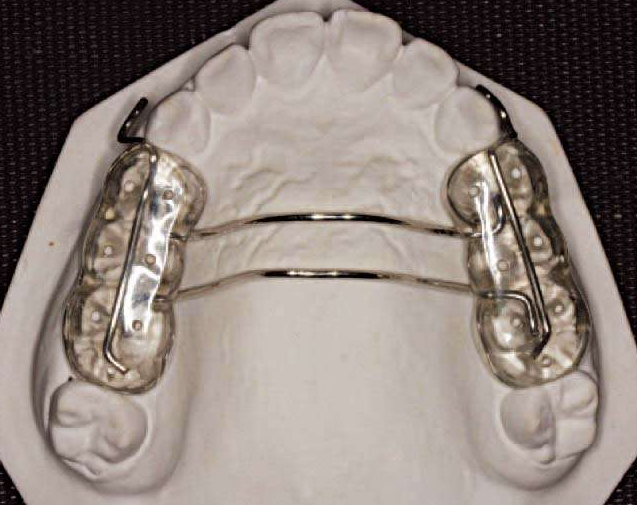

图14 RME

图15 粘结式RME

解决方案:粘结式RME配合前方牵引。